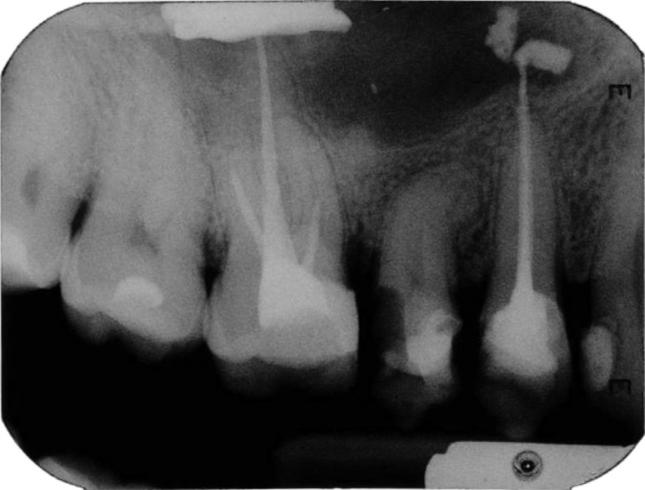

Foreign bodies found in the maxillary sinus include tooth roots, burs, dental impression material, root-filling materials, dental implants, and needles. The purpose of this paper was to present an unusual case of a large foreign body of endodontic origin (root-filling material) removed from the maxillary sinus. A 45-year-old generally healthy male patient reported to the Department of Conservative Dentistry with Endodontics of the Medical University of Silesia, because of orbital and buccal pain on the right side of his face and headaches in the preceding 6 months. Those symptoms were associated with the end of endodontic treatment of teeth 14 and 16. Periapical X-rays, including of teeth 14 and 16, showed the presence of root canal filling with extrusion of endodontic obturation material beyond the apices of tooth 14. In the case of tooth 16, a completely filled palatal canal and incompletely filled buccal canals were found. There was also an irregular dimness at the upper edge of the X-ray image. Panoramic radiography and computed tomography demonstrated a foreign body in the right sinus. Sinus exploration was performed via a surgical procedure conducted using topical anesthesia. The root apices of tooth 14 were resected, and foreign substance was removed. The practitioner did not correctly recognize a complication that occurred during endodontic treatment, which resulted in extrusion of endodontic material beyond the root apices of tooth 14. This case emphasizes the potential impact that an involved maxillary sinus may have on endodontic therapy. Detailed diagnostic identification based on the medical interview, physical and histopathological examinations, and diagnostic imaging allowed rapid surgical intervention and prevented local and general complications. It is important to realize that the range of the periapical X-ray projection is not always sufficient.

在上颌窦中发现的异物包括牙根、牙钻、牙科印模材料、根管充填材料、牙种植体和针头。本文的目的是介绍一例罕见的源自牙髓治疗的大型异物(根管充填材料)从上颌窦取出的病例。一名45岁的健康男性患者因右侧面部眼眶和颊部疼痛以及前6个月的头痛,前往西里西亚医科大学保守牙科与牙髓病科就诊。这些症状与14号和16号牙齿的牙髓治疗结束有关。包括14号和16号牙齿在内的根尖X线片显示根管充填,牙髓充填材料超出了14号牙齿根尖。对于16号牙齿,发现腭根管完全充填,颊根管充填不完全。X线图像上缘还存在不规则的模糊影。全景X线摄影和计算机断层扫描显示右侧上颌窦有异物。通过局部麻醉下的外科手术进行鼻窦探查。切除了14号牙齿的根尖,并取出了异物。该从业者未正确识别牙髓治疗期间发生的并发症,导致牙髓材料超出14号牙齿根尖。该病例强调了受累上颌窦可能对牙髓治疗产生的潜在影响。基于医学问诊、体格检查、组织病理学检查和诊断成像进行详细的诊断识别,有助于快速进行手术干预并预防局部和全身并发症。必须认识到根尖X线投影范围并不总是足够的。